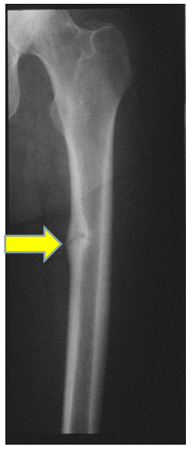

Radiografia da haste femoral em paciente com osteomalácia demonstrando "pseudofratura" (também conhecida como zona de Looser) no aspecto medial da haste femoral média

Do acervo de Bridget Sinnott, MD